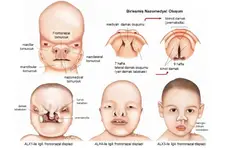

Yenidoğanda Kistik Fibrozis Belirtileri ve Tedavisi Kistik fibrozis (KF), genetik bir hastalık olup, vücuttaki mukus, ter ve sindirim sıvılarının anormal şekilde kalınlaşmasına neden olur. Bu durum, özellikle solunum ve sindirim sistemlerini etkileyerek ciddi sağlık sorunlarına yol açabilir. Yenidoğan döneminde kistik fibrozisin tanınması, erken müdahale ve tedavi açısından son derece önemlidir. Bu makalede, yenidoğanda kistik fibrozis belirtileri ve tedavi yöntemleri detaylı bir şekilde ele alınacaktır. Kistik Fibrozisin Nedenleri Kistik fibrozis, CFTR (Cystic Fibrosis Transmembrane Conductance Regulator) genindeki mutasyonlar sonucu ortaya çıkar. Bu genin normal işleyişi, vücutta mukus salınımını düzenler. Mutasyona uğramış bir CFTR geni, mukusun kalınlaşmasına ve yapışkan hale gelmesine neden olur. Bu durum, akciğerler ve sindirim sistemi gibi organlarda ciddi hasarlara yol açabilir. Yenidoğanda Kistik Fibrozis Belirtileri Yenidoğan döneminde kistik fibrozisin belirtileri genellikle doğumdan hemen sonra veya ilk birkaç ay içinde ortaya çıkar. Bu belirtiler şunlardır:

Sonuç Yenidoğanda kistik fibrozis, erken tanı ve tedavi ile yönetilebilen bir hastalıktır. Belirtilerin farkında olmak ve gerekli testleri zamanında yaptırmak, çocukların sağlıklı bir yaşam sürmelerine yardımcı olabilir. Kistik fibrozisli bireylerin tedavi süreçlerinde aile desteği ve uzman sağlık ekiplerinin işbirliği büyük önem taşımaktadır. Ekstra Bilgiler Kistik fibrozis, genetik bir hastalık olmasına rağmen, toplumda farkındalığın artırılması ve erken teşhis imkanlarının yaygınlaştırılması, hastalığın yönetiminde önemli bir rol oynamaktadır. Yenidoğan tarama programları, kistik fibrozis tanısını hızlı bir şekilde koyarak, tedavi sürecinin erken başlatılmasına olanak tanır. Ayrıca, kistik fibrozisli çocukların eğitim ve sosyal yaşamlarında desteklenmeleri, yaşam kalitelerini artırmak açısından kritik öneme sahiptir. |

Bebeğinizin topuk kanı testi, yenidoğan tarama programları kapsamında yapılan rutin bir işlemdir ve çok önemlidir. Bu test, ciddi metabolik ve genetik hastalıkları erken dönemde tespit etmek amacıyla yapılır. Kistik fibrozis gibi hastalıklar, erken tanı ve tedavi ile çok daha iyi yönetilebilir.